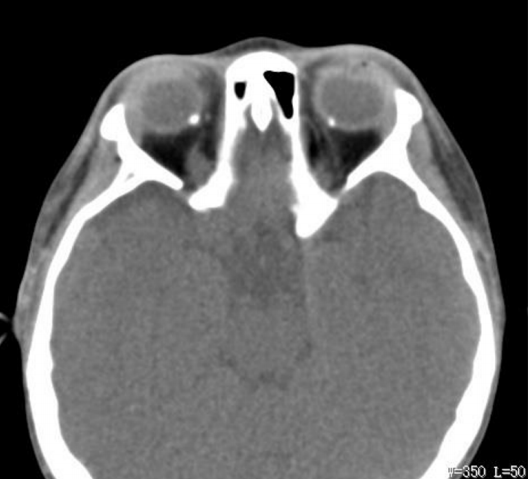

20230608171815_6308.png

图6 患者眼眶CT检查显示:双侧眼球后壁鼻侧致密影,右侧眼上静脉短条形致密影,双侧泪腺睑部增大,右侧筛窦、上颌窦炎,右侧颌面部皮下多发条形软组织密度影

Figure 6 CT examination of the patient’s orbit showed dense shadows on the nasal side of the posterior wall of bilateral eyeballs,short strip dense shadows on the right superior ocular vein, enlarged eyelid of bilateral lacrimal glands, right sigmoid sinus and maxillary sinusitis, and multiple strip soft tissue density shadows under the skin of right maxillofacial area